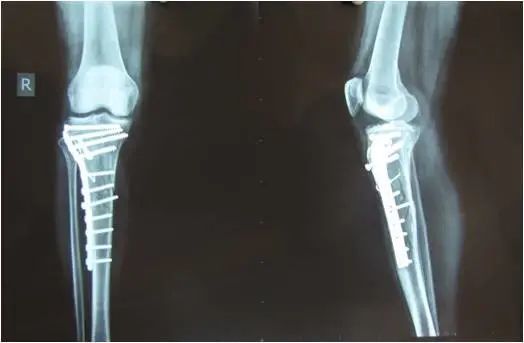

今天门诊来了一位患者,一年前因车祸致右小腿骨折,在当地医院进行骨折切开复位内固定术。术后复查骨折复位良好,可是现在都一年了,复查X光时当地医生告之骨折还没长好,有可能需要再次手术治疗。患者这下傻眼了,非常不理解,手术都做了,而且都一年了怎么就没长好呢?是手术没做好吗?因为不信任当地医院而来我门诊就诊。我给他详细讲解了影响骨折愈合的各种原因,最终患者决定在我科住院再次接受手术治疗。

其实骨折愈合过程是受多种因素影响的一个复杂过程。任何干扰使骨折愈合过程发生改变,都可导致延迟愈合或骨不连。手术只是恢复了骨折对线对位,同时对断端进行了牢固定固定,为骨折愈合创造了条件。但还有很多因素会影响骨折愈合。